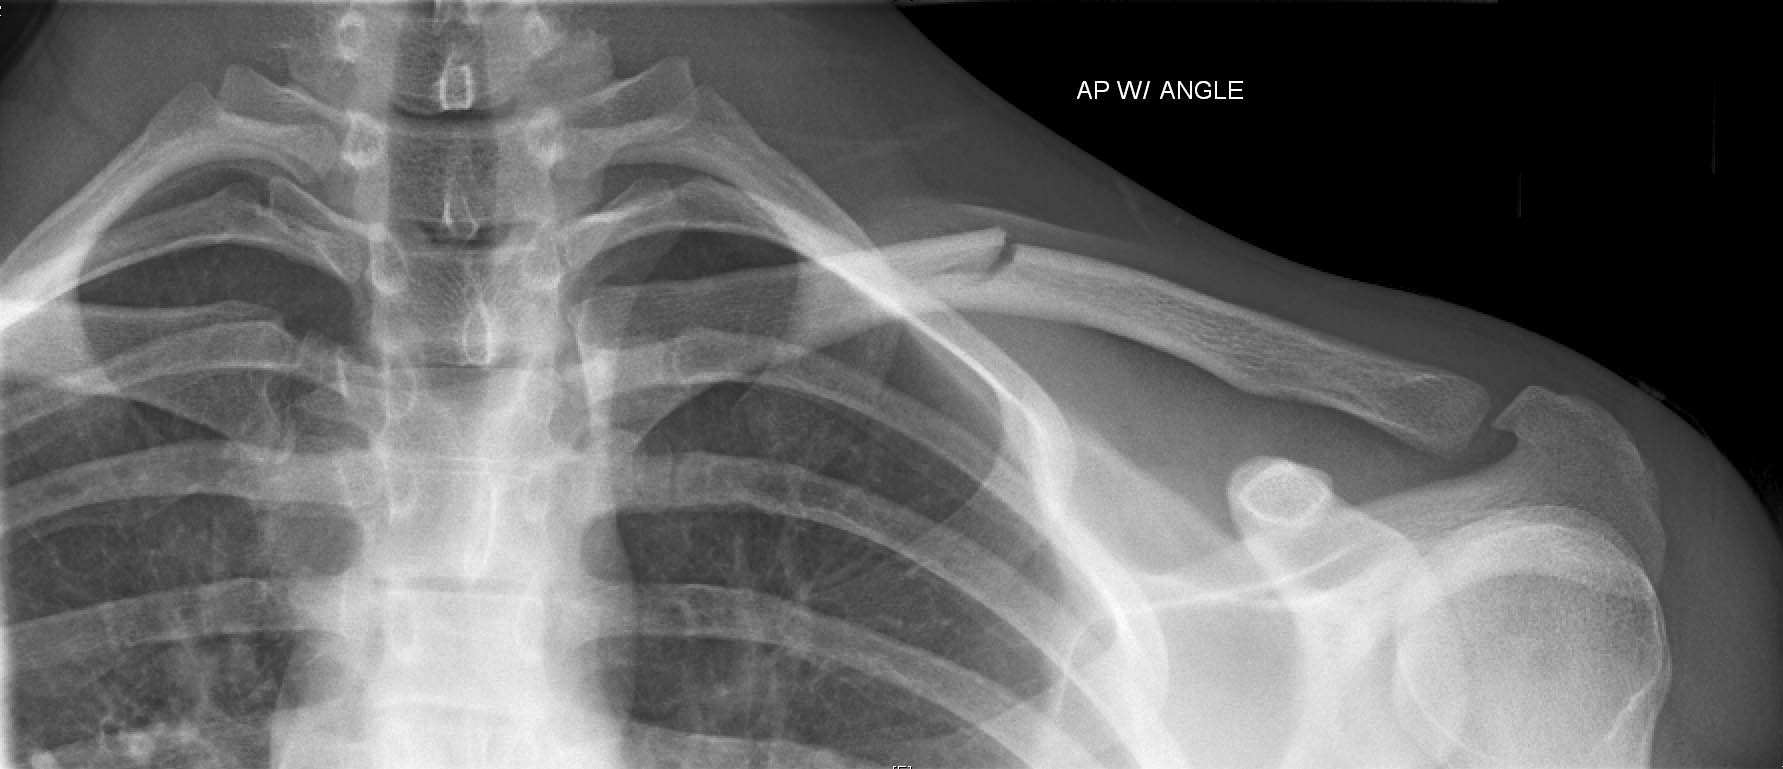

新生小孩锁骨骨折怎么办?新生儿锁骨骨折是新生儿娩出过程中最常的骨折。新生儿锁骨骨折治疗简易,预后良好,没有并发症,故不应采取任何过激的治疗方法新生婴儿的锁骨骨折,大多数是产伤,而且几乎都是顺产的,这种骨折比较常见。

有些出生后,家人并不知道锁骨发生骨折,只是骨折的这一边手臂活动比较少,引起雷注意,一拍片,才发现有骨折。有的是给孩子洗澡穿衣服的时候,孩子哭泣,另一边则没有这样的情况,引起家人都注意,才发现的。也有的家长比较细心,看见锁骨的地方两边不一样,一边明显鼓起来,摸或者按压会引起孩子哭闹挣扎,引起注意,去拍片才发现有骨折。

新生儿锁骨骨折恢复较快,一般都于骨折的一个礼拜出现骨膜增生及骨痂形成,两年内随着小儿的生长发育,肩部增宽,锁骨的畸形均可自行消失,完全恢复原状,不会留有后遗症

绝大多数新生儿锁骨骨折是不需要治疗的,只要这边的手臂穿衣服和洗澡的时候轻柔一些即可。也有的家长一直没发现,知道骨折愈合后,形成骨痂,那个地方鼓了起来,才发现,不过这个时候,孩子已经活动自如了。一般在10天左右,就会愈合,不需要任何治疗。虽然对位对线不好,愈合后有个鼓起来的包包,硬硬的,以后会慢慢塑形,包包会逐渐消失。所以是不需要担心的。